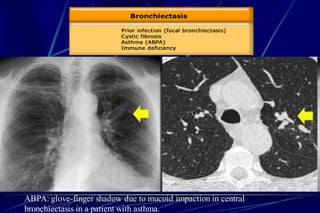

Bronchiectasis

Bronchiectasis is defined as localized bronchial

dilatation. (signet-ring sign)

bronchial wall thickening

lack of normal tapering with visibility of airways in

the peripheral lung

mucus retention in the broncial lumen

associated atelectasis and sometimes air trapping

ABPA: glove-finger shadow due to mucoid impaction in central

bronchiectasis in a patient with asthma.

Signet-Ring Sign

A signet-ring sign represents an axial cut of a dilated bronchus

(ring) with its accompanying small artery (signet).

Tram Tracks

Bronchial dilation with lack of tapering .